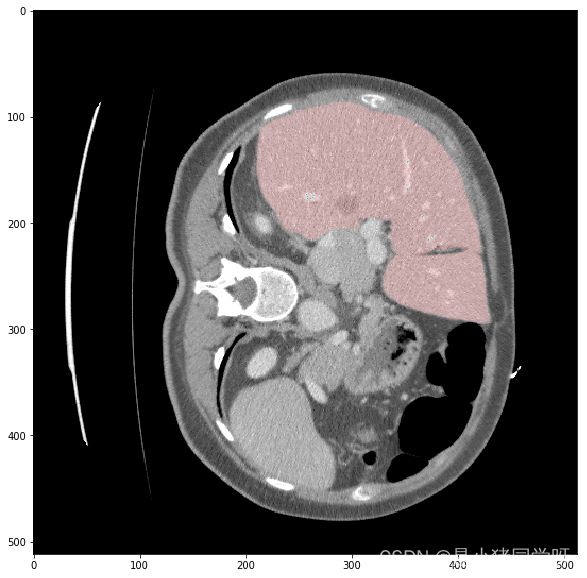

经过测试,肝脏和肝脏肿瘤分割系统的各项功能都能够正常工作,满足用户需求。在白盒测试方面,覆盖了网络结构、特征提取、特征映射、损失函数等方面,没有发现明显的问题。在黑盒测试方面,采用了等价类划分、边界值分析、因果图和错误推测等方法,测试结果表明系统的各项指标均符合要求,没有发现明显的问题。

本次测试结果表明,肝脏和肝脏肿瘤分割系统的各项功能都能够正常工作,满足用户需求。在白盒测试和黑盒测试方面,测试覆盖了网络结构、特征提取、特征映射、损失函数、上传CT影像、查看分割结果、后处理、性能评估、恢复测试、安全测试、强度测试和性能测试等方面,测试结果表明系统的各项指标均符合要求,没有发现明显的问题。